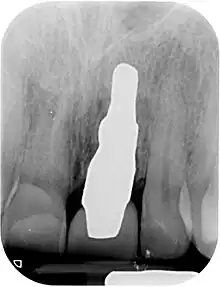

A root-analogue dental implant (RAI) – also known as a truly anatomic dental implant, or an anatomical/custom implant – is a medical device to replace one or more roots of a single tooth immediately after extraction. In contrast to common titanium screw type implants, these implants are custom-made to exactly match the extraction socket of the specific patient. Thus there is usually no need for surgery.

RAIs are custom made to perfectly fit the tooth socket of a specific patient immediately after tooth extraction. Therefore every implant is unique. As an optimised root-form it is much more than a simple 1:1 replica of a tooth. Since it exactly fills the gap left after the tooth is extracted, surgery is rarely needed. The implant can be produced from a copy of the extracted tooth, an impression of the tooth socket, or from a CT scan or CBCT scan.[3] The advantage of a CBCT scan is that the implant can be produced before extraction. With the former methods, it takes one or two days to fabricate an implant.

- Natural form: a custom milled anatomic implant replicates the natural form of a tooth, so it simply fits into the tooth socket. Like the original tooth, a root analogue implant can have single- and multi-rooted forms.